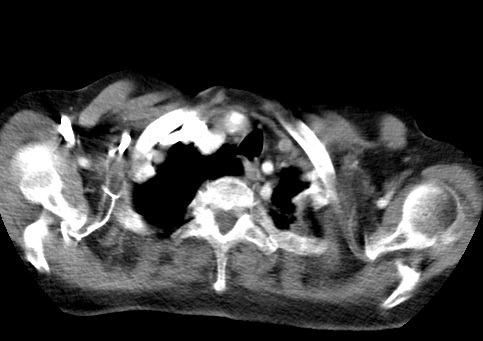

标题: CT23982:女67岁,胸部扫描时发现,甲状腺瘤? [打印本页]

标题: CT23982:女67岁,胸部扫描时发现,甲状腺瘤?

右侧甲状腺腺瘤!支持!不排除甲状腺癌可能!建议手术切除!

右侧甲状腺占位性病变,性质待定(甲状腺腺瘤?);建议:必要时行进一步检查。

右侧甲状腺占位性病变,性质待定(甲状腺腺瘤?);建议穿刺活检。

右侧甲状腺占位性病变,甲状腺腺瘤可能,建议穿刺活检。